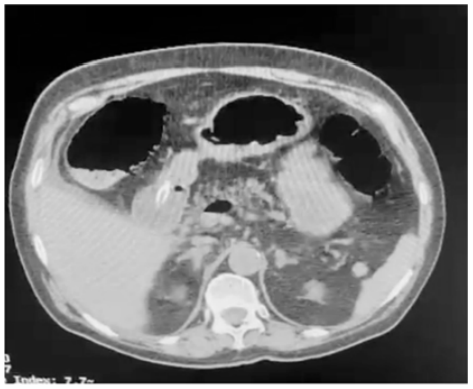

Um paciente de oitenta anos de idade, já com grau de perda de funcionalidade, com períodos de esquecimento, chegou ao pronto-socorro com queda importante do estado geral, com poucas informações objetivas, porém com dor ao exame físico de abdômen. Difícil interpretação dos sinais de irritação peritoneal. Realizou a tomografia abaixo.

Enunciado 3313718-3

A principal causa desse achado é o(a)